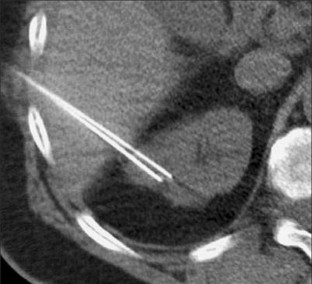

Fig. 2